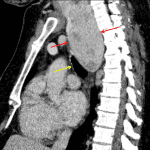

- Large right posterior mediastinal mass measuring 10 cm in craniocaudal span with mass effect on the trachea

- Posterior mediastinal mass (thyroid goiter)

Large right posterior mediastinal mass measuring 10 cm in craniocaudal span with mass effect on the trachea. Recommend chest CT for further evaluation.

- It is important to try to separate mediastinal masses based on location in the anterior, middle, or posterior mediastinum

- Thyroid goiters can extend into the anterior or posterior aspect of the superior mediastinum

- This case is a good example of the cervicothoracic sign, which indicates that if a mediastinal mass has clearly defined margins above the level of the clavicles, it must be in the posterior mediastinum (the anterior and middle mediastinum does not extend above the level of the clavicles)

- A recent publication by the International Thymic Malignancy Interest Group (ITMIG) defines the three mediastinal compartments as prevascular (bounded posteriorly by the pericardium), visceral (bounded anteriorly by the pericardium and posteriorly by an imaginary line drawn through each thoracic vertebral body 1 cm from its anterior margin), and paravertebral

- Think about the following categories with posterior (paravertebral) mediastinal masses:

- Neurogenic abnormalities: neurogenic tumors (nerve sheath, parasympathetic, sympathetic), neurenteric cysts, meningocele

- Bone tumors/metastases

- Infection – e.g. paraspinal abscess

- Trauma – e.g. hematoma

- Extramedullary hematopoiesis

- This case turned out to be a large thyroid goiter (see CT image below).